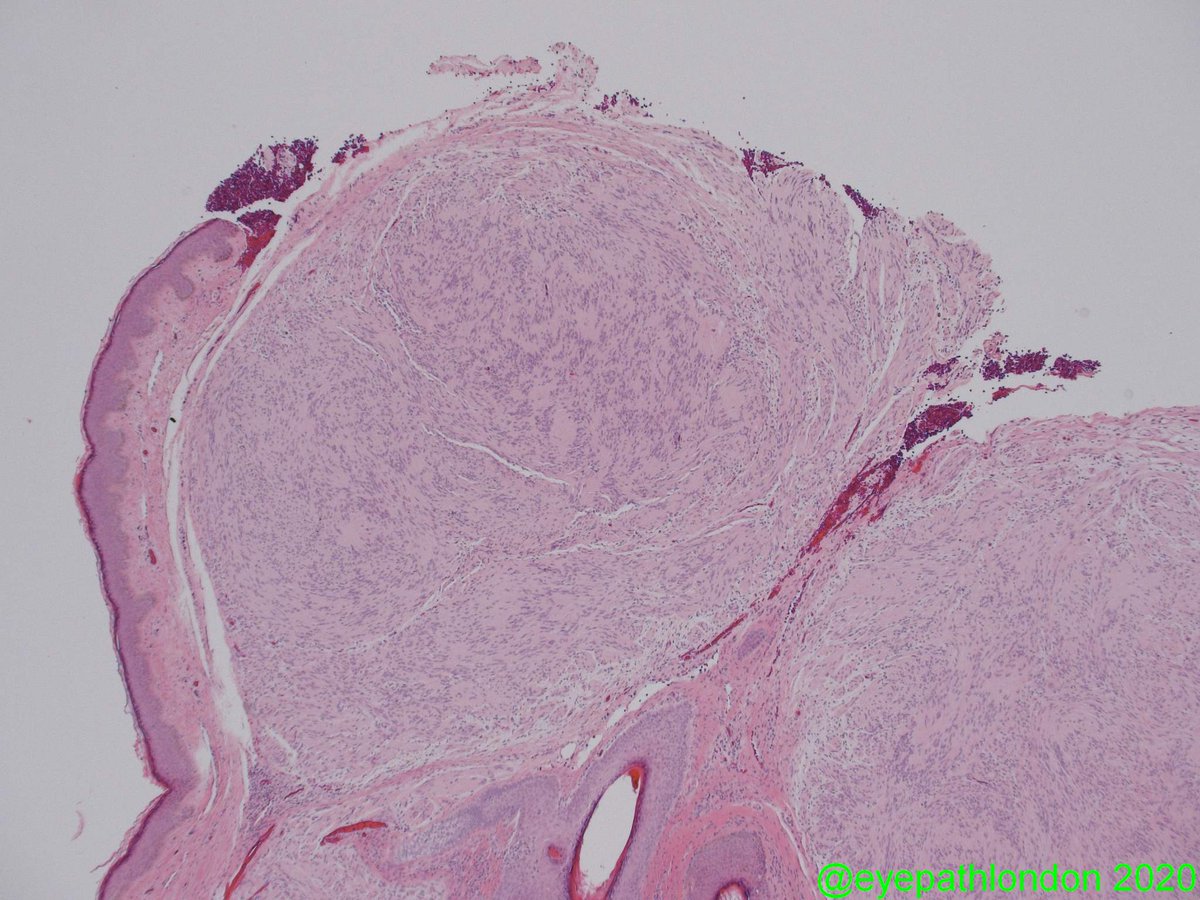

1/? Enucleations can be intimidating specimens! Confirm appropriate laterality by assessing attached muscles (sup rectus & sup oblique = most helpful) & position of ciliary vessels (run horizontally). Mark sup aspect /w pen/sharpie to maintain orientation

2/? I am currently working on a short how-to post for grossing enucleations for melanoma. To be continued...